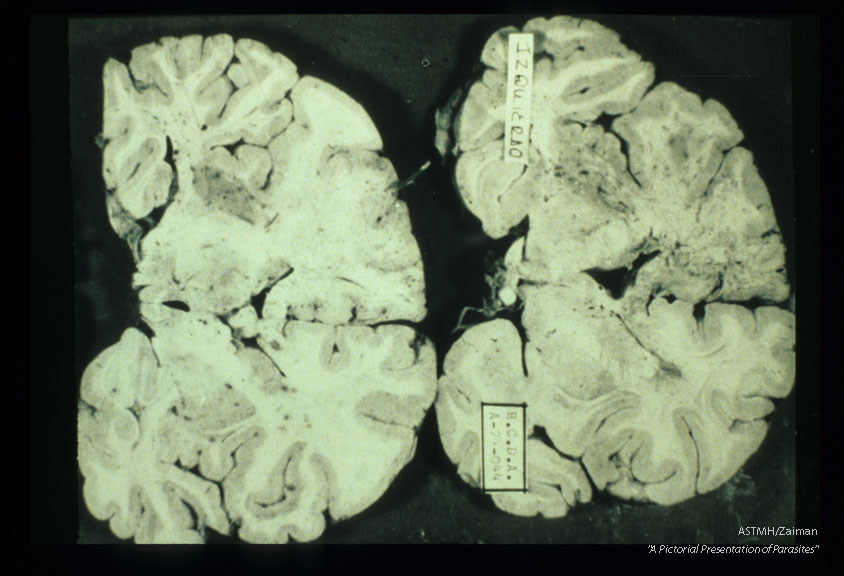

Brain slices showing massive destruction due to granulomatous amoebic encephalopathy.

Acanthamoeba castellanii

Description: Brain slices showing massive destruction due to granulomatous amoebic encephalopathy.